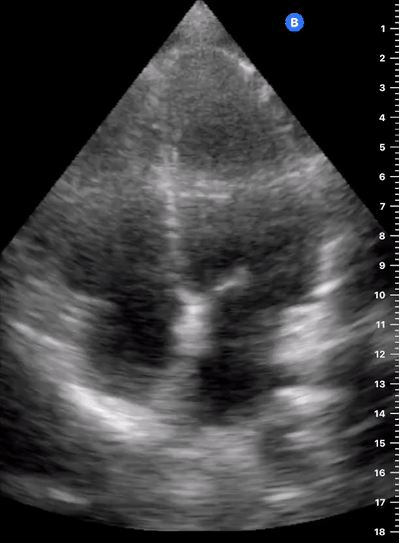

APICAL FOUR-CHAMBER VIEW

This view looks at the heart from the apex. When done properly, it achieves a horizontal cut of the heart that demonstrate all four chambers simultaneously. Consequently, its main utility is to assess the relationship between LV and RV. Beware, differentiating the chambers by ventricle size or thickness is not recommended, and it could lead to confusion in case of RV enlargement.

ORIENTATION & TECHNIQUE

Place the transducer at the apex beat and angle it towards the right scapula. The correct image results from sliding the probe until the interventricular septum is in the middle of the screen, vertically dividing both sides of the heart. If using a cardiac preset, the probe’s marker points towards the patient’s left arm. Simpler, in this view, the probe notch should meet the marking on the screen, which is fundamental to avoid confusion.